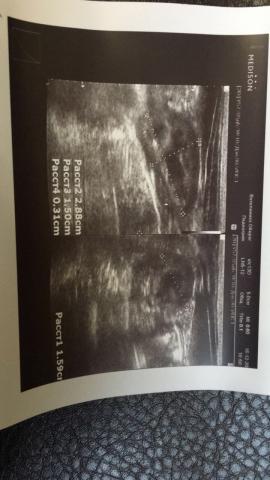

Если можно, то немного подробнее. На основании чего вам поставили такой диагноз, только на основании проведенного УЗИ? Может быть, собаке брали какие-то анализы? Если да, то выложите, пожалуйста, здесь их результаты. Если только данные УЗИ, то это разговор ни о чем (я имею ввиду панкреатит). Гастрит по данным УЗИ вообще не ставят.

К сожалению, ничего не могу рассмотреть. Попробуйте сами прочесть описание с фото. Если сможете, сделайте снимок более качественным. Или можно снять крупнее по частям. Может быть, тогда буквы будут видны более четко.

Спасибо, фотографии четкие. Я все прочитал. Как я и думал, там и "не пахнет" никаким гастродуоденитом, а тем более, панкреатитом.